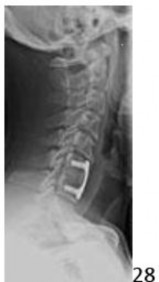

9. # The radiographic findings shown at the C5-6 disk above the C6-7 fusion in Figure 28 are most commonly associated with what part of the surgical technique?

5. # The upper end of the plate being in close proximity to the adjacent disk

DISCUSSION: When the upper border of the plate is located in close proximity to the cephalad adjacent disk, there is a higher incidence of osteophyte formation. The clinical implications of this are not yet understood. Screw penetration or needle puncture may influence the degenerative process at that disk, but this would manifest itself more as narrowing and end plate changes as opposed to an osteophyte forming

along the anterior annulus. The role of the longus colli and periosteal dissection are not fully elucidated but are less commonly associated with this finding.

The Preferred Response to Question # 28 is 5.